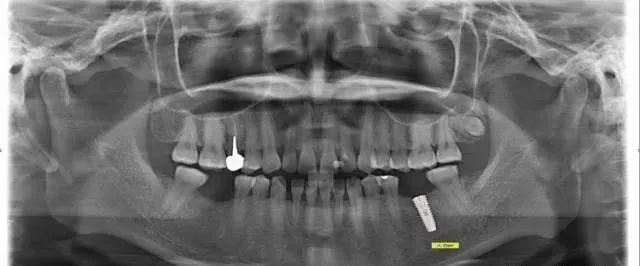

这个种植病例选择了长度为13mm的种植体(OSSTEM系统),种植术后拍摄全景片再次测量我们就会发现,原本13mm的种植体在全景片上被放大至16.89mm,几乎相差4mm。

所以种植医生要对患者的全景片能够有足够的经验判断,考虑到种植手术的安全选择一个比较合适的种植体型号。如果全景片不能很好判断,那么还可以给患者拍摄一张CT,在CT上精确测量可用骨的高度。